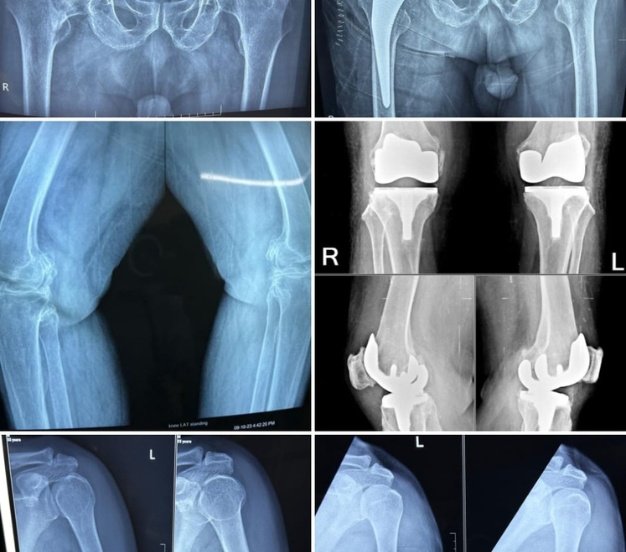

Operative X-rays